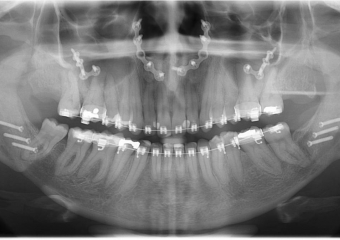

Raio x inicial

Raio x após a cirurgia